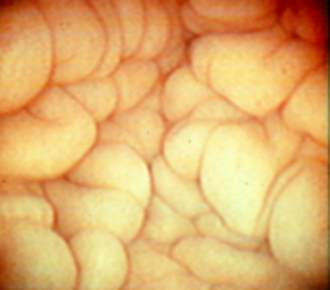

Healthy endometrium